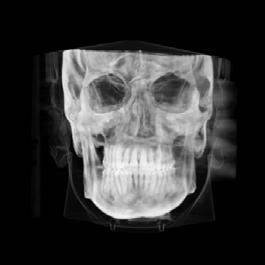

Clinical evaluation showed a mild Class III skeletal pattern with a constricted maxilla, mildly dolichofacial and straight

profile (Figure 1). Full adult dentition was present with all third molars extracted. Maxillary and mandibular incisors were normoclined. The maxillary midline coincided with the facial midline, and the mandibular midline was 2 mm to the right of the facial midline. There was a 2 mm to 5 mm lateral open bite on the right side from the second molar to the lateral incisor, and the maxillary occlusal plane was canted to the left of the interpupillary line. A lateral tongue thrust into the open bite was noted on swallow.

The right side was in posterior crossbite and there was an edge-to-edge anterior bite with wear on the maxillary central incisors. Mild gingival recession was noted, but soft tissue was generally within normal limits. CBCT analysis found no radiographic evidence of osteoarthritis in the TMJ joints, nor osseous or apical pathology involving the maxillary or mandibular teeth. His airway was not constricted. Initial report from the myofunctional therapist indicated that the patient never developed a mature swallow sequence and had a bilateral posterior tongue thrust.

Figure 1. Initial records.